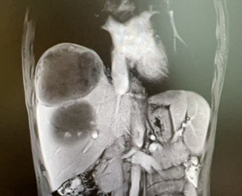

新辅助(两次HAIC和两个周期靶免治疗)后MR

由于病人一般情况较好,肝功能良好(Child-pugh A级),经多学科会诊临床确认肿瘤为IIb期肝细胞癌,属于可切除性肝癌,但存在高危复发因素,建议先行新辅助治疗后手术切除。经两次肝动脉关注化疗(HAIC)(奥沙利铂+5-Fu+亚叶酸钙方案)和两个周期的靶向免疫治疗(仑伐替尼+帕博利珠单抗方案),第二次介入造影是肿瘤血供不明显,第二次介入治疗4周后复查CT提示肿瘤缩小不明显但坏死征象明显,经MRI证实仍有少许血供,于是经多学科会诊后决定行前入路右半肝切除术。